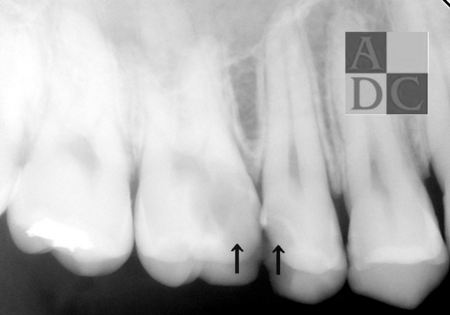

≪初診時≫

矢印の部分の虫歯が痛く 抜髄処置(神経を取る治療)となりました。

≪第一小臼歯根管充填時≫

まず、単根管の小臼歯の根管充填写真です。

根尖まで 白い根管充填材が

満たしているのが確認できます。